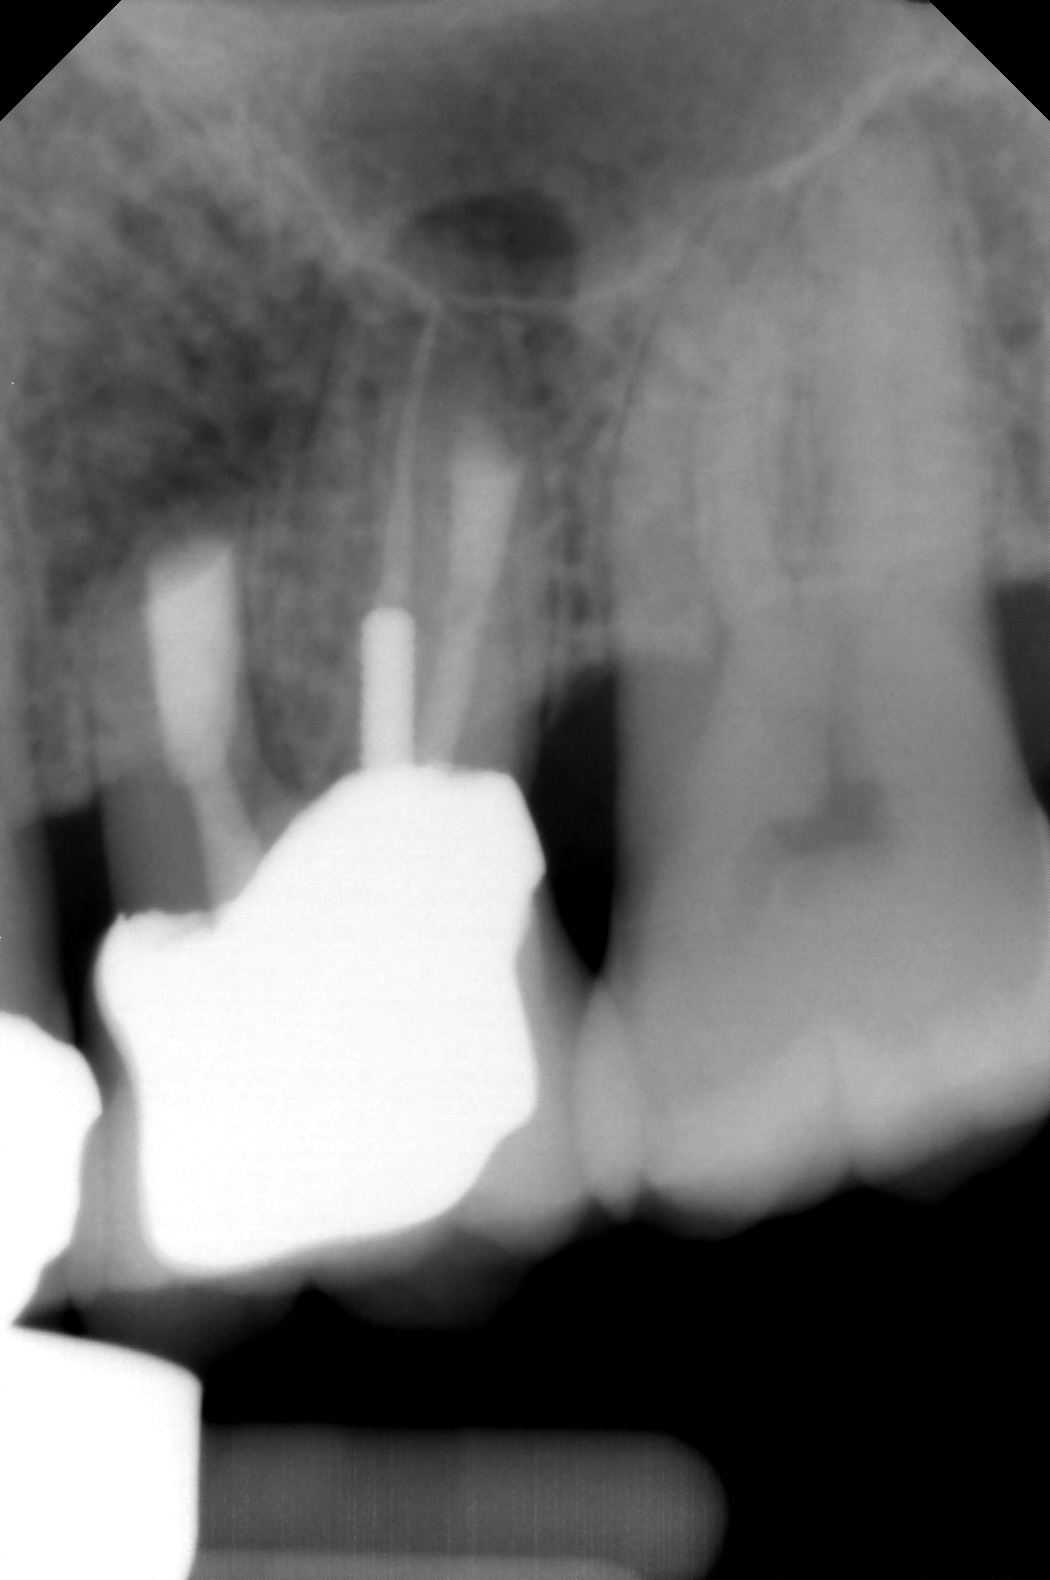

Clinical procedure: Regeneration of the endodontic pulp space is indicated for cases with very thin dentinal walls and an open apex that is more than 1 mm in diameter radiographically (Figure 4). Disinfection of the root canal system is performed using sodium hypochlorite irrigation followed by a triple antibiotic paste dressing that is left in place for 1 week. At the second visit, ethylenediaminetetraacetic acid (EDTA) is used to condition the dentin walls, which results in the release of growth factors, and bleeding is stimulated in the periapical tissues (where stem cells are located), with the aim of filling the pulp space with a stable blood clot, which would serve as the scaffold. MTA is then placed at the canal orifice in contact with the clot to protect it from coronal microleakage (Figure 5 and Figure 6). In time, the clot should be replaced with a reparative tissue of variable composition, and the root walls should continue to thicken due to the deposition of a dentin-like material on the pre-existing root dentin27,28 (Figure 7 and Figure 8).

Fig 4. Preoperative radiograph showing aggressive external root resorption and thin dentinal walls.

Figure 4

Fig 5. Working length confirmation.

Figure 5

Fig 6. Postoperative radiograph.

Figure 6

Fig 7. 1-year follow-up showing a healthy lamina dura and root development.

Figure 7

Fig 8. 3-year follow-up showing continued root development.

Figure 8